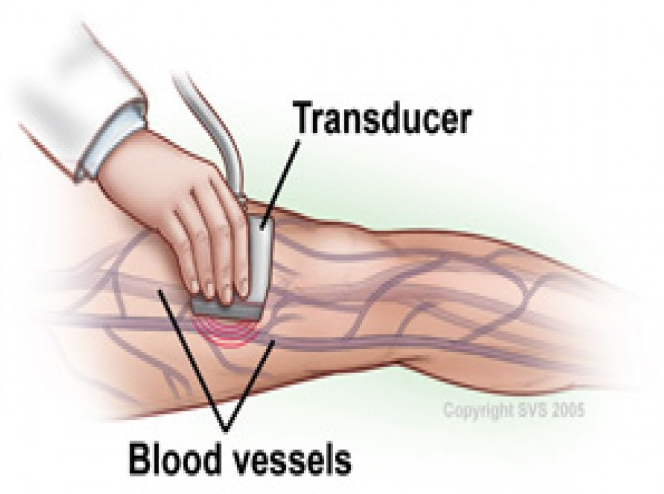

سونوگرافی کالر داپلر یکی از روشهای تصویربرداری غیرتهاجمی و پیشرفته پزشکی است که با استفاده از امواج ماورای صوت، جهت و سرعت جریان خون را در عروق بدن به صورت رنگی نمایش میدهد و نقش مهمی در تشخیص بیماریهای قلبی و عروقی، مشکلات کلیوی و کبدی، و حتی ارزیابی سلامت جنین ایفا میکند.

در این روش امواج فراصوت به بدن ارسال میشوند و پس از برخورد با گلبولهای خونی بازتاب مییابند؛ دستگاه با تحلیل این بازتابها، وضعیت جریان خون را به صورت رنگی (معمولاً قرمز و آبی بر اساس جهت و سرعت) نشان میدهد. این قابلیت، ارزیابی سریع هرگونه انسداد، لخته یا ناهنجاری عروقی را ممکن میسازد.